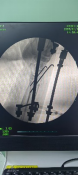

術中透視

患者男性,54歲,外傷致右側脛腓骨開放性骨折8小時,局部可見右側脛骨骨折近端露出···